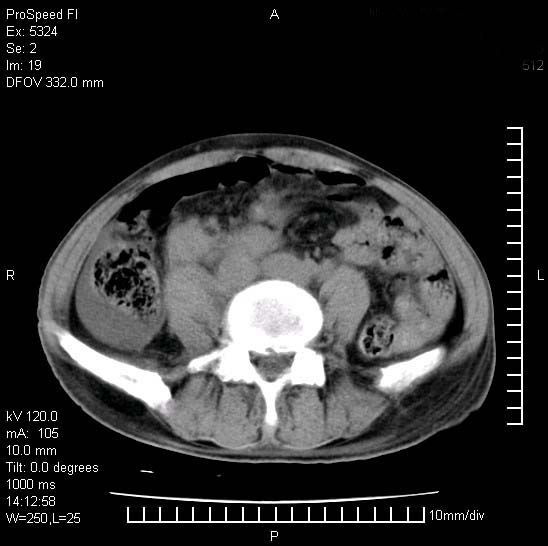

患者阴囊肿大14月,腰痛2个月,咳嗽,咳痰1周,患者现在肾功异常,做增强有些担心,我们用的是欧乃派克.

右侧肾癌伴腹膜后淋巴结转移!

右侧肾癌后腹膜转移,腹腔少量积液

腹膜后淋巴结肿大包饶腔静脉,双肾病变,建议增强

双肾均有软组织密度舯物,腹膜后淋巴结肿大包饶腔静脉------考虑为恶性占位病变,转移瘤可能。

左肾也有问题呀///

支持:双肾均见软组织密度肿块影,腹膜后淋巴结肿大包绕腔静脉------考虑为恶性占位病变,转移瘤可能。

1)考虑双肾恶性肿瘤(肾癌?)。2)腹膜后淋巴结肿大,多为肿瘤转移所致。

腹腔积液,双肾均有稍高密度肿块,主动脉旁广泛淋巴结肿大,融合,无显著肿块坏死征像,多考虑淋巴瘤累及双肾,不排除肾癌伴转移(肾癌这么大应该较多坏死了),另阴囊肿大,不知是实质肿大还是阴囊积液,如是是积液,多为腹腔肿块压近睾丸静脉所致,如是是实性的,多为淋巴瘤

1、淋巴瘤,双肾转移瘤;2、双侧肾癌,伴有腹膜后淋巴结转移。

双肾周围及腹膜后改变符合恶性病变,现在关键是要明确阴囊肿大的原因,是否为肿瘤性病变.如阴囊为恶性肿瘤那一切用转移即可解释,如阴囊为水肿改变,那需重新分析检查明确.

双肾均有软组织肿块伴腹膜后淋巴结肿大融合,右侧结肠旁沟积液;考虑恶性肿瘤。转移瘤?淋巴瘤?

阴囊肿大是实质性的么,为什么不扫阴囊,此扫描做的是什么部位,肾脏没包括全,也可以考虑生殖系统肿瘤转移

双肾增大,腹膜后多发肿大淋巴结影.首先考虑淋巴瘤.

双肾增大,结合腹膜后淋巴结肿大,考虑双肾恶性肿瘤并转移可能。

双肾癌并腹膜后淋巴结转移

考虑恶性淋巴瘤侵及双肾,腹膜后淋巴结肿大。